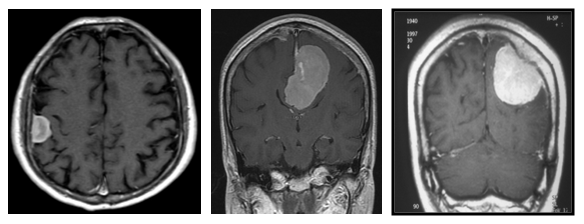

※ 형광유도물질을 이용한 교모세포종 수술에서 뇌종양세포만 붉은색을 띄고 정상조직은 푸른색을 띄어 종양을 선택적으로 절제하는 데 도움을 받고 있음특히, 최근에 여러 종료의 항암화학요법을 위한 치료제가 개발되었으나, 뇌조직에는 혈류-뇌 장벽(blood-brain barrier)라는 특별한 구조로 인해, 뇌종양의 사용에는 제한적인 효과만 보고 있습니다. 이들 중 Temozolomide라는 경구 항암제는 뇌침투율이 높고 부작용이 적어서, 이를 이용한 항암-방사선 병합치료가 표준치료로써 많이 이용되고 있습니다.2. 뇌수막종뇌수막종(meningioma)는 가장 흔히 접하는 원발성 뇌종양 중의 하나로, 주로 성인에서 발생하며, 2:1의 비율로 여성에게서 많이 발생하는 것으로 알려져 있습니다. 생기는 위치는 천막상부가 90% 이상이나 천막하부 및 드물게 뇌실내에서도 발생합니다. 아래 그림에서 보듯이 뇌수막종의 임상증상은 종양의 위치와 크기에 따라 달라지게 됩니다. 주로는 두개강내압 항진에 의한 증상과 신경세포의 국소적 자극으로 나눌 수 있으며, 최근 들어 CT, MRI의 보급이 늘면서 증상이 없이 우연히 발견되는 경우가 많습니다.가장 대표적인 치료법은 수술적 방법을 통한 완전제거입니다. 하지만, 이는 뇌수막종의 위치나 크기, 신경학적 장애 위험 등을 모두 고려해야 합니다. 최근에는 잔여 종양이나 재발 종양에 감마나이프 수술 등의 방사선 수술을 시행함으로써 종양조절률을 높이고 신경학적 장애를 적게 남기는 방법도 많이 이용되고 있습니다.뇌수막종의 경우에는 양성종양이 대부분을 이루고 있지만, 세포분화도가 높은 이형성 수막종(atypical meningioma), 악성 수막종(anaplastic meningioma) 등이 있으므로, 정밀한 병리학적 진단이 필요하며, 경우에 따라서는 추가 치료가 필요한 경우도 있습니다.

※ 뇌수막종의 전형적인 MRI 소견 – 균일한 조영증강을 보이며, 주변 뇌조직과는 비교적 경계가 분명한 형태를 보임, 크기나 생긴 위치에 따라 수술적 접근법이 달라지며, 추가 치료 여부도 달라지게 됨3. 뇌하수체 종양뇌하수체 종양은 뇌하수체및 뇌하수체 줄기부위에서 발생하는 종양들을 일컬으며 가장 많은 것은 뇌하수체 선종과 두개인두종입니다.